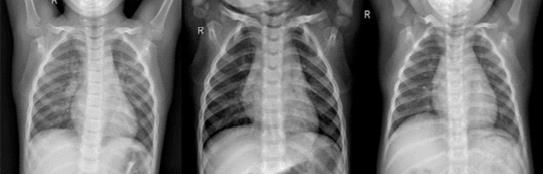

Thedatabaseisfurtherdividedintothreefolders(train, test,andval)withsubfoldersforeachimagecategory (Pneumonia/General).Figure1showsafewinstances of common and pneumonia photos that have been scaled to a static size. Due to the low amount of exposureinpatients,chestX-rayimagesalwaysshow symptomsoflimitedbrightness,andchestX-rayimages alwayshaveblack,white,andgreypants.

Thelungsareonbothsidesofthethoraciccavity,and the lung area is plainly visible on an X-ray since it is virtuallyblack.Theheart,whichissituatedbetweenthe lungs, appears practically as white as X-rays can go through it entirely. Because bones are comprised of proteinandareexceedinglydense,X-rayscannotpass through them, leaving the bones virtually white. Furthermore,theboneshavedistinctedges.

-1:Examplesfromthedataset.(a)normal cases, (b) pneumoniacases